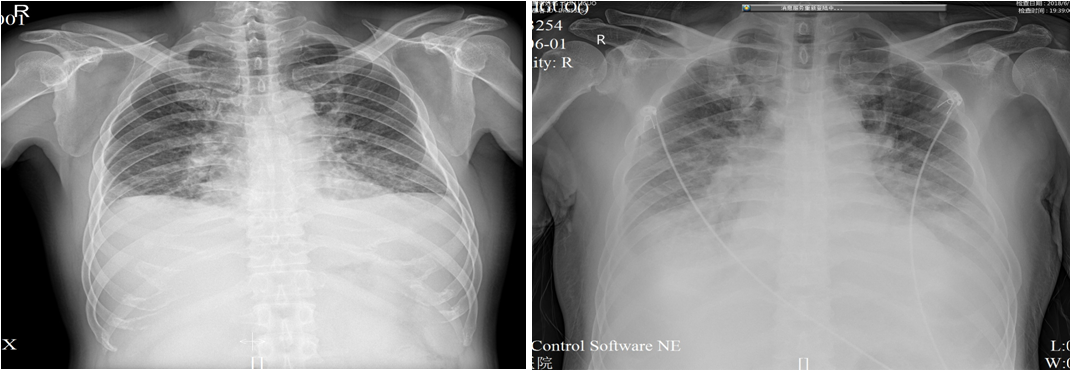

5.27及6.1查胸片示:双肺肺水肿,双侧大量胸腔积液,明显进展